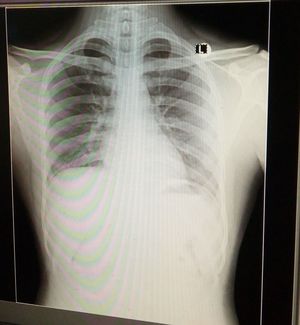

Not PTX for sure, on the left side it looks like bronchitis and the described symptoms might lead us to the same conclusion. The patience’s diaphragm is a little bit up - I don’t know why - that is the reason why you can see the liver so clearly

In x-ray we can see bullas that can confirm our diagnosis and sometimes we have plural effusion in both sides that in this case bulles are bilateral and spread all over two lungs